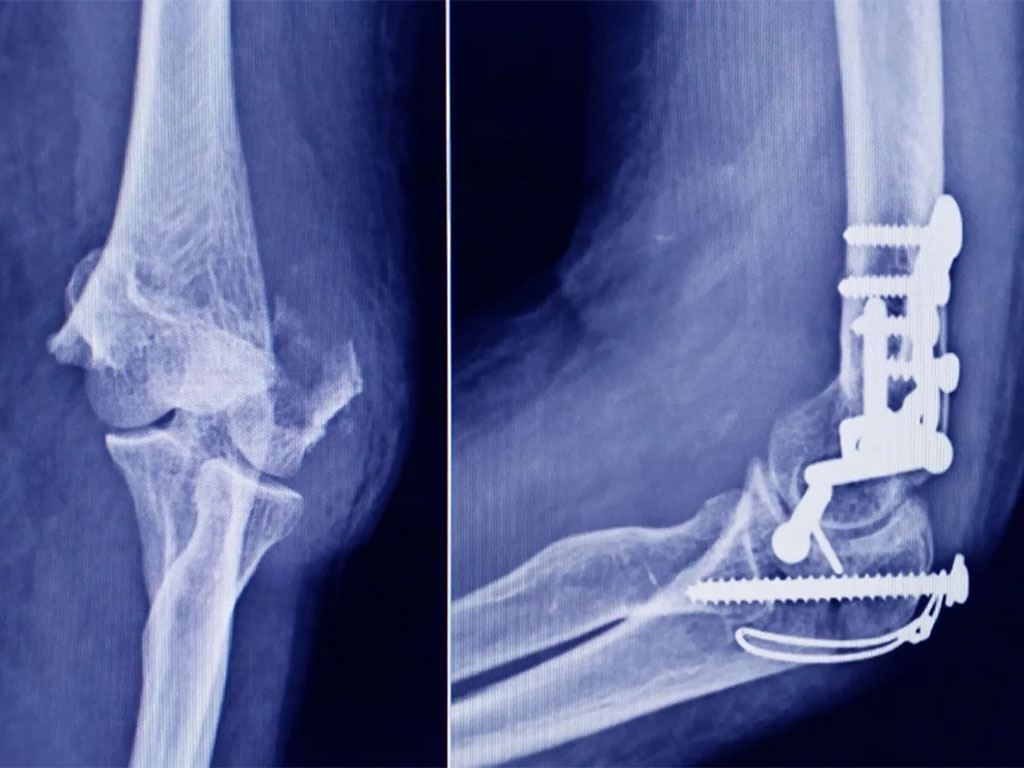

Se trata de un tornillo utilizado en cirugías traumatológicas, que fue detectado durante una inspección de control de mercado realizada en una ortopedia ubicada en la ciudad de San Miguel de Tucumán.

Dicho tornillo es producido por la firma Stryker Corporation, que se encuentra registrada ante ANMAT bajo el PM 594-139. Luego de la inspección, se exhibió la muestra recolectada ante la responsable técnica de dicha empresa, quien afirmó que se trataba de un producto falsificado.

Las autoridades de la ANMAT dieron a conocer las características del producto para su advertencia: STRYKER 10 mm X 28 mm - BIOABSORBABLE - ACL INTERFERENCE SCREW - REF 234-010-067 - LOT 90905.